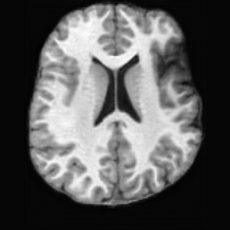

(a)PathologicalInput ImageSynthSR [18]Brain-ID [28]UNA [30]USBHealthyGround TruthRefer to captionRefer to captionRefer to captionRefer to captionRefer to captionRefer to captionRefer to captionRefer to captionRefer to captionRefer to captionRefer to captionRefer to captionRefer to captionRefer to captionRefer to captionRefer to captionRefer to captionRefer to captionRefer to captionRefer to captionRefer to captionRefer to captionRefer to captionRefer to caption(b)HealthyInput ImageConditionalLesion MaskUNA [30]USBRefer to captionRefer to captionRefer to captionRefer to captionRefer to captionRefer to captionRefer to captionRefer to captionRefer to captionRefer to captionRefer to captionRefer to captionRefer to captionRefer to captionRefer to captionRefer to caption

Figure 5: Comparison of bidirectional brain editing. (a) pathology-to-healthy, the circles and arrows highlight lesion regions and unsuccessful reconstructions; (b) healthy-to-pathology. Note that SynthSR and Brain-ID cannot perform healthy-to-pathology editing.

Pathology-to-Healthy Editing. Fig. 5 (a) presents comparison results on four input brain images with lesions of varying sizes, shapes, and densities. All competing models, although specialized for healthy brain image synthesis, struggle to reconstruct pathological regions, especially near lesion boundaries. In contrast, USB accurately reconstructs the corresponding healthy brain, even in challenging cases with large, high-density lesions where normal brain structures are almost completely obscured (last row). Tab. 2 provides a quantitative comparison for pathology-to-healthy editing, where USB achieves the best performance across all three datasets, demonstrating the effectiveness of its unified framework in reconstructing healthy brains from pathological inputs. Additional results are in Suppl. B.

Healthy-to-Pathology Editing. As shown in Fig. 5 (b), given a healthy brain image paired with a random lesion mask, USB seamlessly embeds the lesion into the healthy anatomy, producing realistic pathological appearances consistent with surrounding structural context. Yet UNA’s syntheses are visually unrealistic, with the conditioned lesion mask simply overlaid as a parallel layer onto the healthy brain. Tab. 3 further demonstrates USB’s superior performance. The evaluation was conducted on 100 pairs of lesion masks and healthy brains, with real stroke images